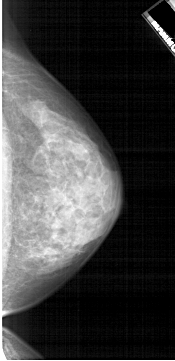

A_1914_1.RIGHT_MLO

RIGHT_MLO LINES 5491 PIXELS_PER_LINE 2431 BITS_PER_PIXEL 12 RESOLUTION 43.5 NON_OVERLAY